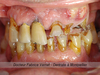

Cas cliniques n°5 : Perte de toutes les dents par maladie parodontale

Avant : parodontologie agressive terminale. Toutes les dents vont être avulsées. Nous allons placer six implants « technique all on six » et mettre en place une prothèse vissée sur implants toute céramique pour remplacer toutes les dents du maxillaire sup. Après, sourire retrouvé avec des dents en céramiques dont la taille correspond aux dents originelles de la patiente.